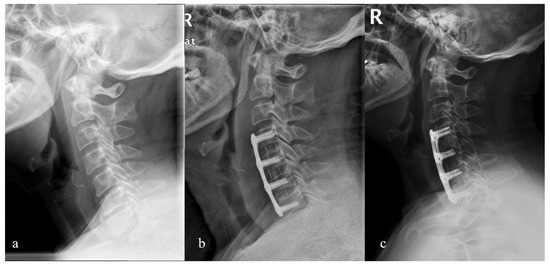

| C2-C7 Cobb (°) | |||

| Preop | 10.8 ± 8.1 | 11.1 ± 7.9 | 0.331 |

| Postop | 15.7 ± 7.4 | 24.8 ± 8.1 | 0.011 |

| Last FU | 12.5 ± 5.7 | 18.6 ± 6.9 | 0.023 |

| Fused segment Cobb (°) | |||

| Preop | 6.1 ± 6.8 | 5.9 ± 7.9 | 0.667 |

| Postop | 12.4 ± 7.1 | 19.8 ± 8.2 | 0.014 |

| Last FU | 9.5 ± 6.6 | 13.9 ± 7.4 | 0.025 |

| Fused segment disc wedge (°) | |||

| Preop | 5.8 ± 5.1 | 6.1 ± 6.9 | 0.564 |

| Postop | 11.3 ± 7.2 | 18.1 ± 7.9 | 0.012 |

| Last FU | 8.1 ± 6.8 | 13.6 ± 7.5 | 0.021 |

| C2-C7 SVA (mm) | |||

| Preop | 28.4 ± 11.3 | 30.1 ± 14.4 | 0.248 |

| Postop | 30.2 ± 14.6 | 28.2 ± 15.7 | 0.145 |

| Last FU | 31.7 ± 13.9 | 29.6 ± 16.5 | 0.233 |